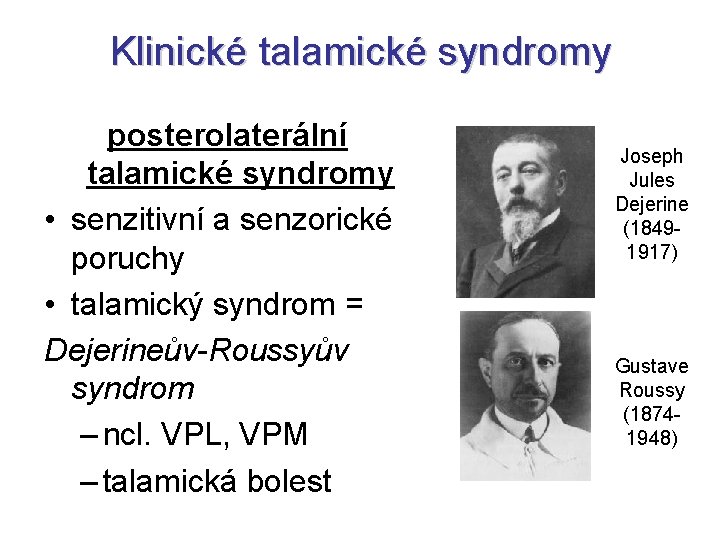

Klinické talamické syndromy posterolaterální talamické syndromy • senzitivní a senzorické poruchy • talamický syndrom = Dejerineův-Roussyův syndrom – ncl. VPL, VPM – talamická bolest Joseph Jules Dejerine (18491917) Gustave Roussy (18741948)